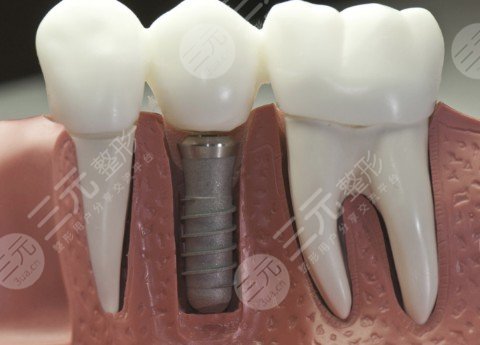

种植牙的利与弊较为明X。种植牙也叫人工种植牙,由下部分的种植体和上部分的牙冠两部分组成,并不是真的种上自然牙齿。首先是价格较高:种植牙相较于其他的牙齿修复技术,因为成本较高,所以在临床上收费也是比其他的牙齿修复技术要高一些。其次是特殊人群无法做种植牙:健康的成人已经完成骨骼和牙齿的发育,可以正常接受种植牙修正,但是只有在基本健康状况良好的情况下才能接受种植牙修正,健康状态不佳的求美者则不建议接受种植牙修正。较后就是修正时间较长:种植牙完成后的修正,依据不同部位,修正时间不同,从3个月到6个月不等,修正时间一般长于其他传统修正方法。应该根据自身情况,选择适合自己的牙齿修正方法。

一、不损坏周围牙齿。种植牙修复不需要磨除缺失位置的邻牙,而是将植体植入牙槽骨中,待植体与牙槽骨结合后,再在种植体上安装烤瓷牙冠,对口腔中其他的牙齿损伤较小。